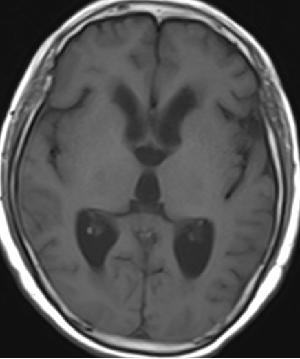

2013-8-8 CT

2013-8-7 脑室腹腔分流术,初压130

2013-8-8 仍诉头痛

2013-8-10 腰穿测压150mmH2O